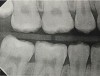

Fig 6. Three thin soft dental picks were used simultaneously for SDF proximal surface saturations in a teenaged patient (Fig 3). After 60 seconds, the treated regions were covered with 5% fluoride varnish (Fig 4). A comparison can be seen of pre-SDF-treatment bitewing films (Fig 5) and 8-month post-SDF bitewing films (Fig 6) for the patient shown in Fig 3 and Fig 4. Radiolucencies were similar or improved, except for contact of maxillary first and second molars.

Figure 6

Interproximal insertion of SDF is demonstrated in different patients in Figure 3 through Figure 11. Various diameters and brands of soft dental picks may be used depending on the closeness of the proximal surfaces and ease of insertion; for example, some picks are designed for use in wider spaces between teeth. This protocol also offers versatility. Figure 3, for example, shows the simultaneous use of three thin soft dental picks to saturate proximal surfaces with SDF in a teenaged patient; the treated regions were subsequently covered with fluoride varnish (Figure 4). This patient was initially treated in April 2019 (Figure 5), with an identical re-application 3 months later. As shown in Figure 6, the December 2019 bitewing film revealed good results with the possible exception of the contact regions of the maxillary first and second molars. New SDF application was completed in the December appointment.

Fig 3. Three thin soft dental picks were used simultaneously for SDF proximal surface saturations in a teenaged patient (Fig 3). After 60 seconds, the treated regions were covered with 5% fluoride varnish (Fig 4). A comparison can be seen of pre-SDF-treatment bitewing films (Fig 5) and 8-month post-SDF bitewing films (Fig 6) for the patient shown in Fig 3 and Fig 4. Radiolucencies were similar or improved, except for contact of maxillary first and second molars.